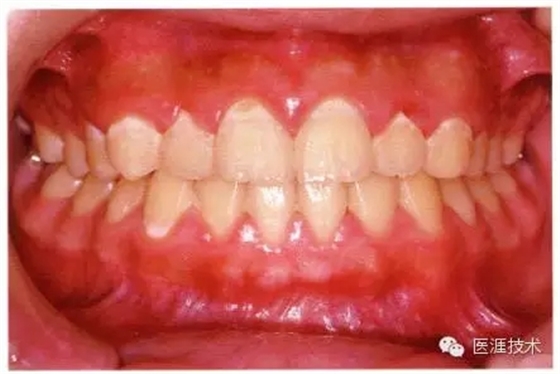

健康且正常的牙周組織臨床圖像

50歲女性的健康口腔內(nèi)部

圖為50歲女性,無特殊全身疾病,不抽煙。持續(xù)保養(yǎng)6年。無填充物等問題,依照患者本人要求持續(xù)觀察。牙周組織臉頰側(cè)雖見部分萎縮,但X線牙片顯示牙間無骨吸收現(xiàn)象,保持著比較健康的狀態(tài)。